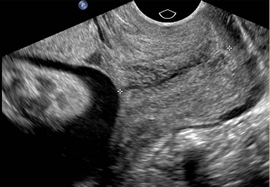

What best describes this image?

CorrectIncorrect -